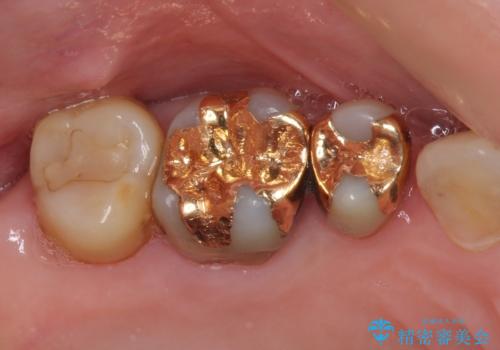

- 奥歯の裏側がしみるとのことで来院された患者様です。

矯正治療による歯肉退縮がおき、歯根にまで虫歯が波及していました。

虫歯が大きかったため、フルジルコニアクラウンにて補綴することとしました。